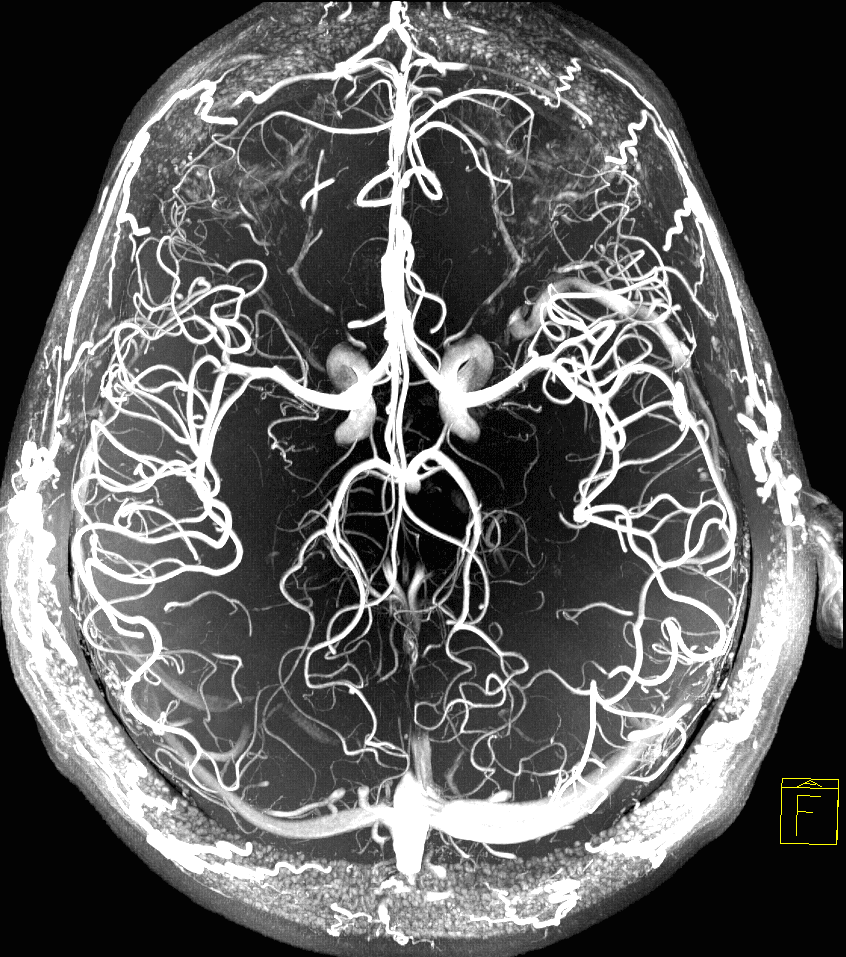

МРТ или КТ сосудов

МРТ сосудов головного мозга и КТ-ангиография сосудов головного мозга - это два очень информативных метода обследования сосудистой системы головного мозга. Принцип получения изображений при магнитно-резонансной томографии строится на эффекте ядерного магнитного резонанса, то есть колебаний атомов водорода в магнитном поле томографа. Томограммы при КТ сосудов головного мозга получаются за счет рентгенологического облучения. МРТ сосудов относится к очень щадящим и безболезненным формам диагностики. Для исследования сосудистого русла не делают никаких проколов и не вводят никакого вредного или вызывающего аллергическую реакцию состава. Компьютерная томография -более опасный для здоровья пациента метод диагностики, но его информативность в некоторых случаях выше магнитно-резонансной ангиографии. Когда МРТ сосудов головного мозга лучше, чем КТ сосудов? Информативные преимущества МРТ сосудов головного мозга сопоставимы с традиционной ангиографией и КТ-ангиографией, но в отличие от них, в ход

МРТ сосудов головного мозга и КТ-ангиография сосудов головного мозга - это два очень информативных метода обследования сосудистой системы головного мозга. Принцип получения изображений при магнитно-резонансной томографии строится на эффекте ядерного магнитного резонанса, то есть колебаний атомов водорода в магнитном поле томографа. Томограммы при КТ сосудов головного мозга получаются за счет рентгенологического облучения. МРТ сосудов относится к очень щадящим и безболезненным формам диагностики. Для исследования сосудистого русла не делают никаких проколов и не вводят никакого вредного или вызывающего аллергическую реакцию состава. Компьютерная томография -более опасный для здоровья пациента метод диагностики, но его информативность в некоторых случаях выше магнитно-резонансной ангиографии.

Информативные преимущества МРТ сосудов головного мозга сопоставимы с традиционной ангиографией и КТ-ангиографией, но в отличие от них, в ходе этой процедуры не используют ионизирующее излучение или нефротоксичные йодсодержащие контрасты. При МРТ, в отличие от КТ, изображение кровеносных сосудов получается без обязательного введения контраста.